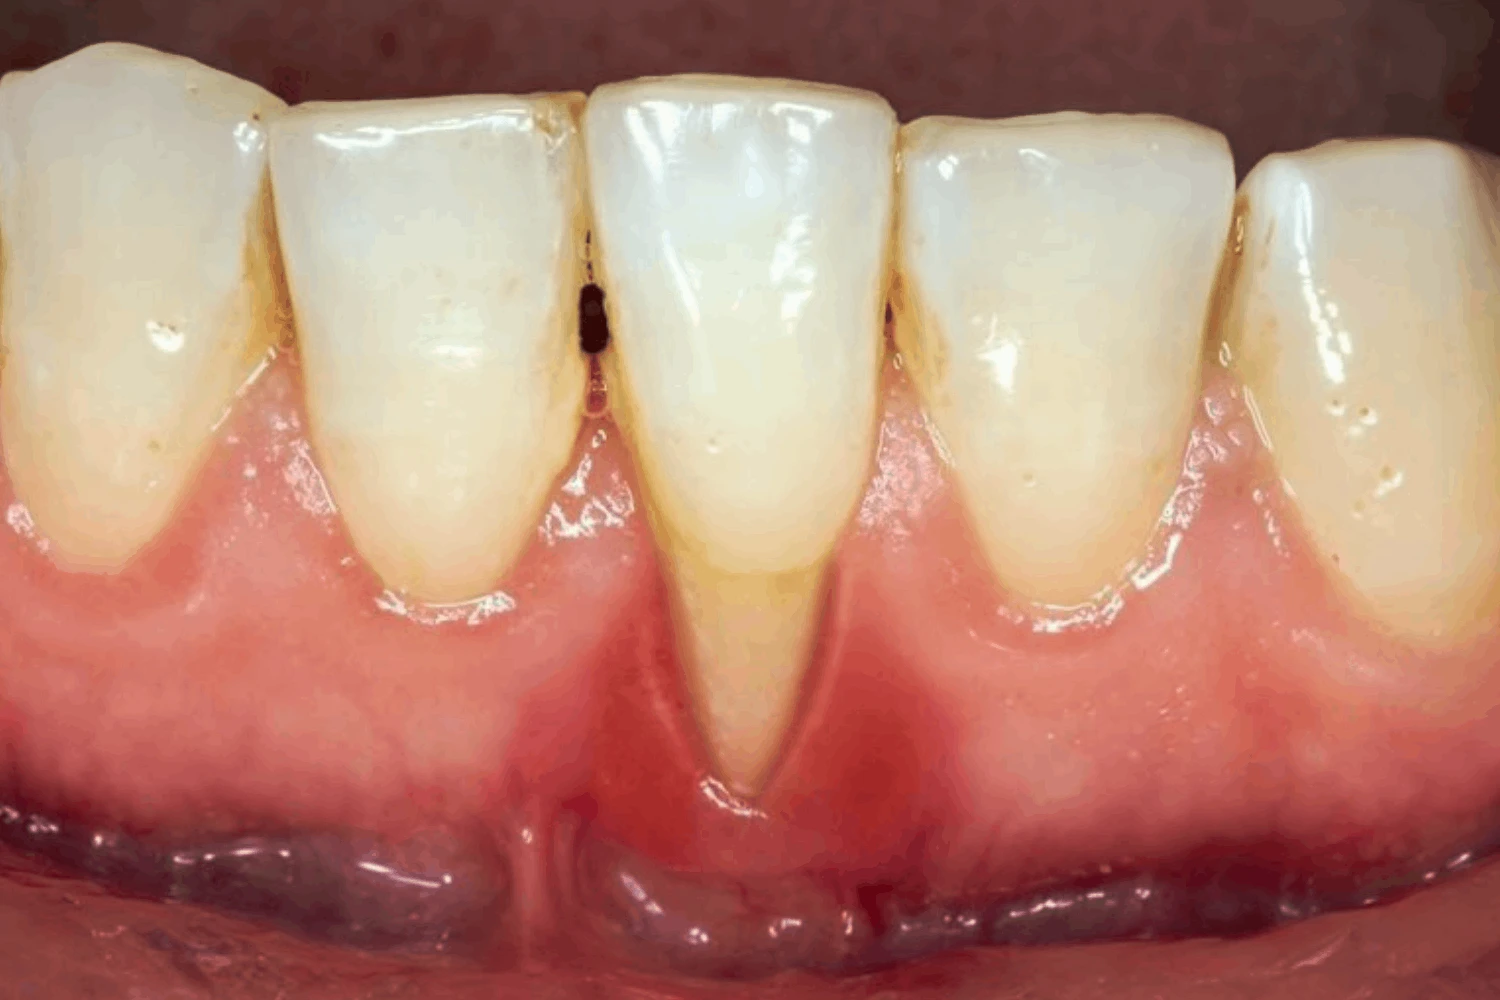

- Chân răng phía dưới mão sứ bị lộ ra, khiến răng trông dài hơn so với các răng khác hoặc so với thời điểm mới bọc răng sứ

- Nướu quanh răng sứ co lại, teo nhỏ, hoặc di chuyển về phía chóp chân răng, không còn ôm sát khít vào cổ răng sứ

- Viền nướu tại vị trí răng sứ có dấu hiệu viêm nhiễm như sưng đỏ, phồng rộp, đau nhức âm ỉ, hoặc dễ chảy máu khi chải răng

- Trong một số trường hợp, bạn có thể nhìn thấy rõ đường hoàn tất (viền) của mão sứ, thậm chí là phần cùi răng thật bên trong